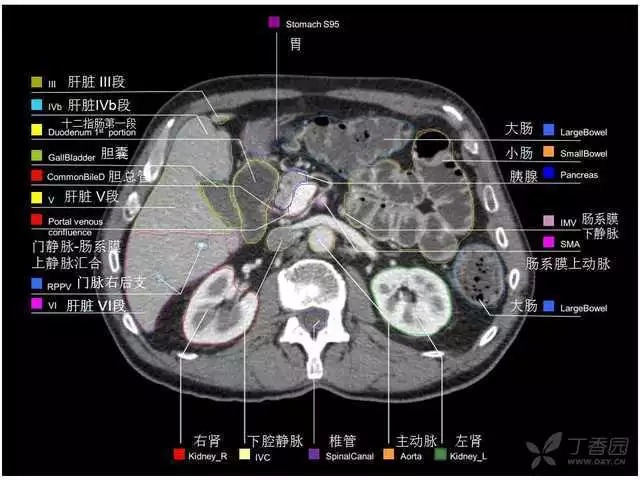

腹部肝脏高清CT断层的图谱

全腹部高清CT图谱,淋巴结彩色图谱,血管解剖图谱大汇总!

肝段,肝内管道的分布规律

美国放射学会ACR官网,对肝脏的区域和节段解剖学概述